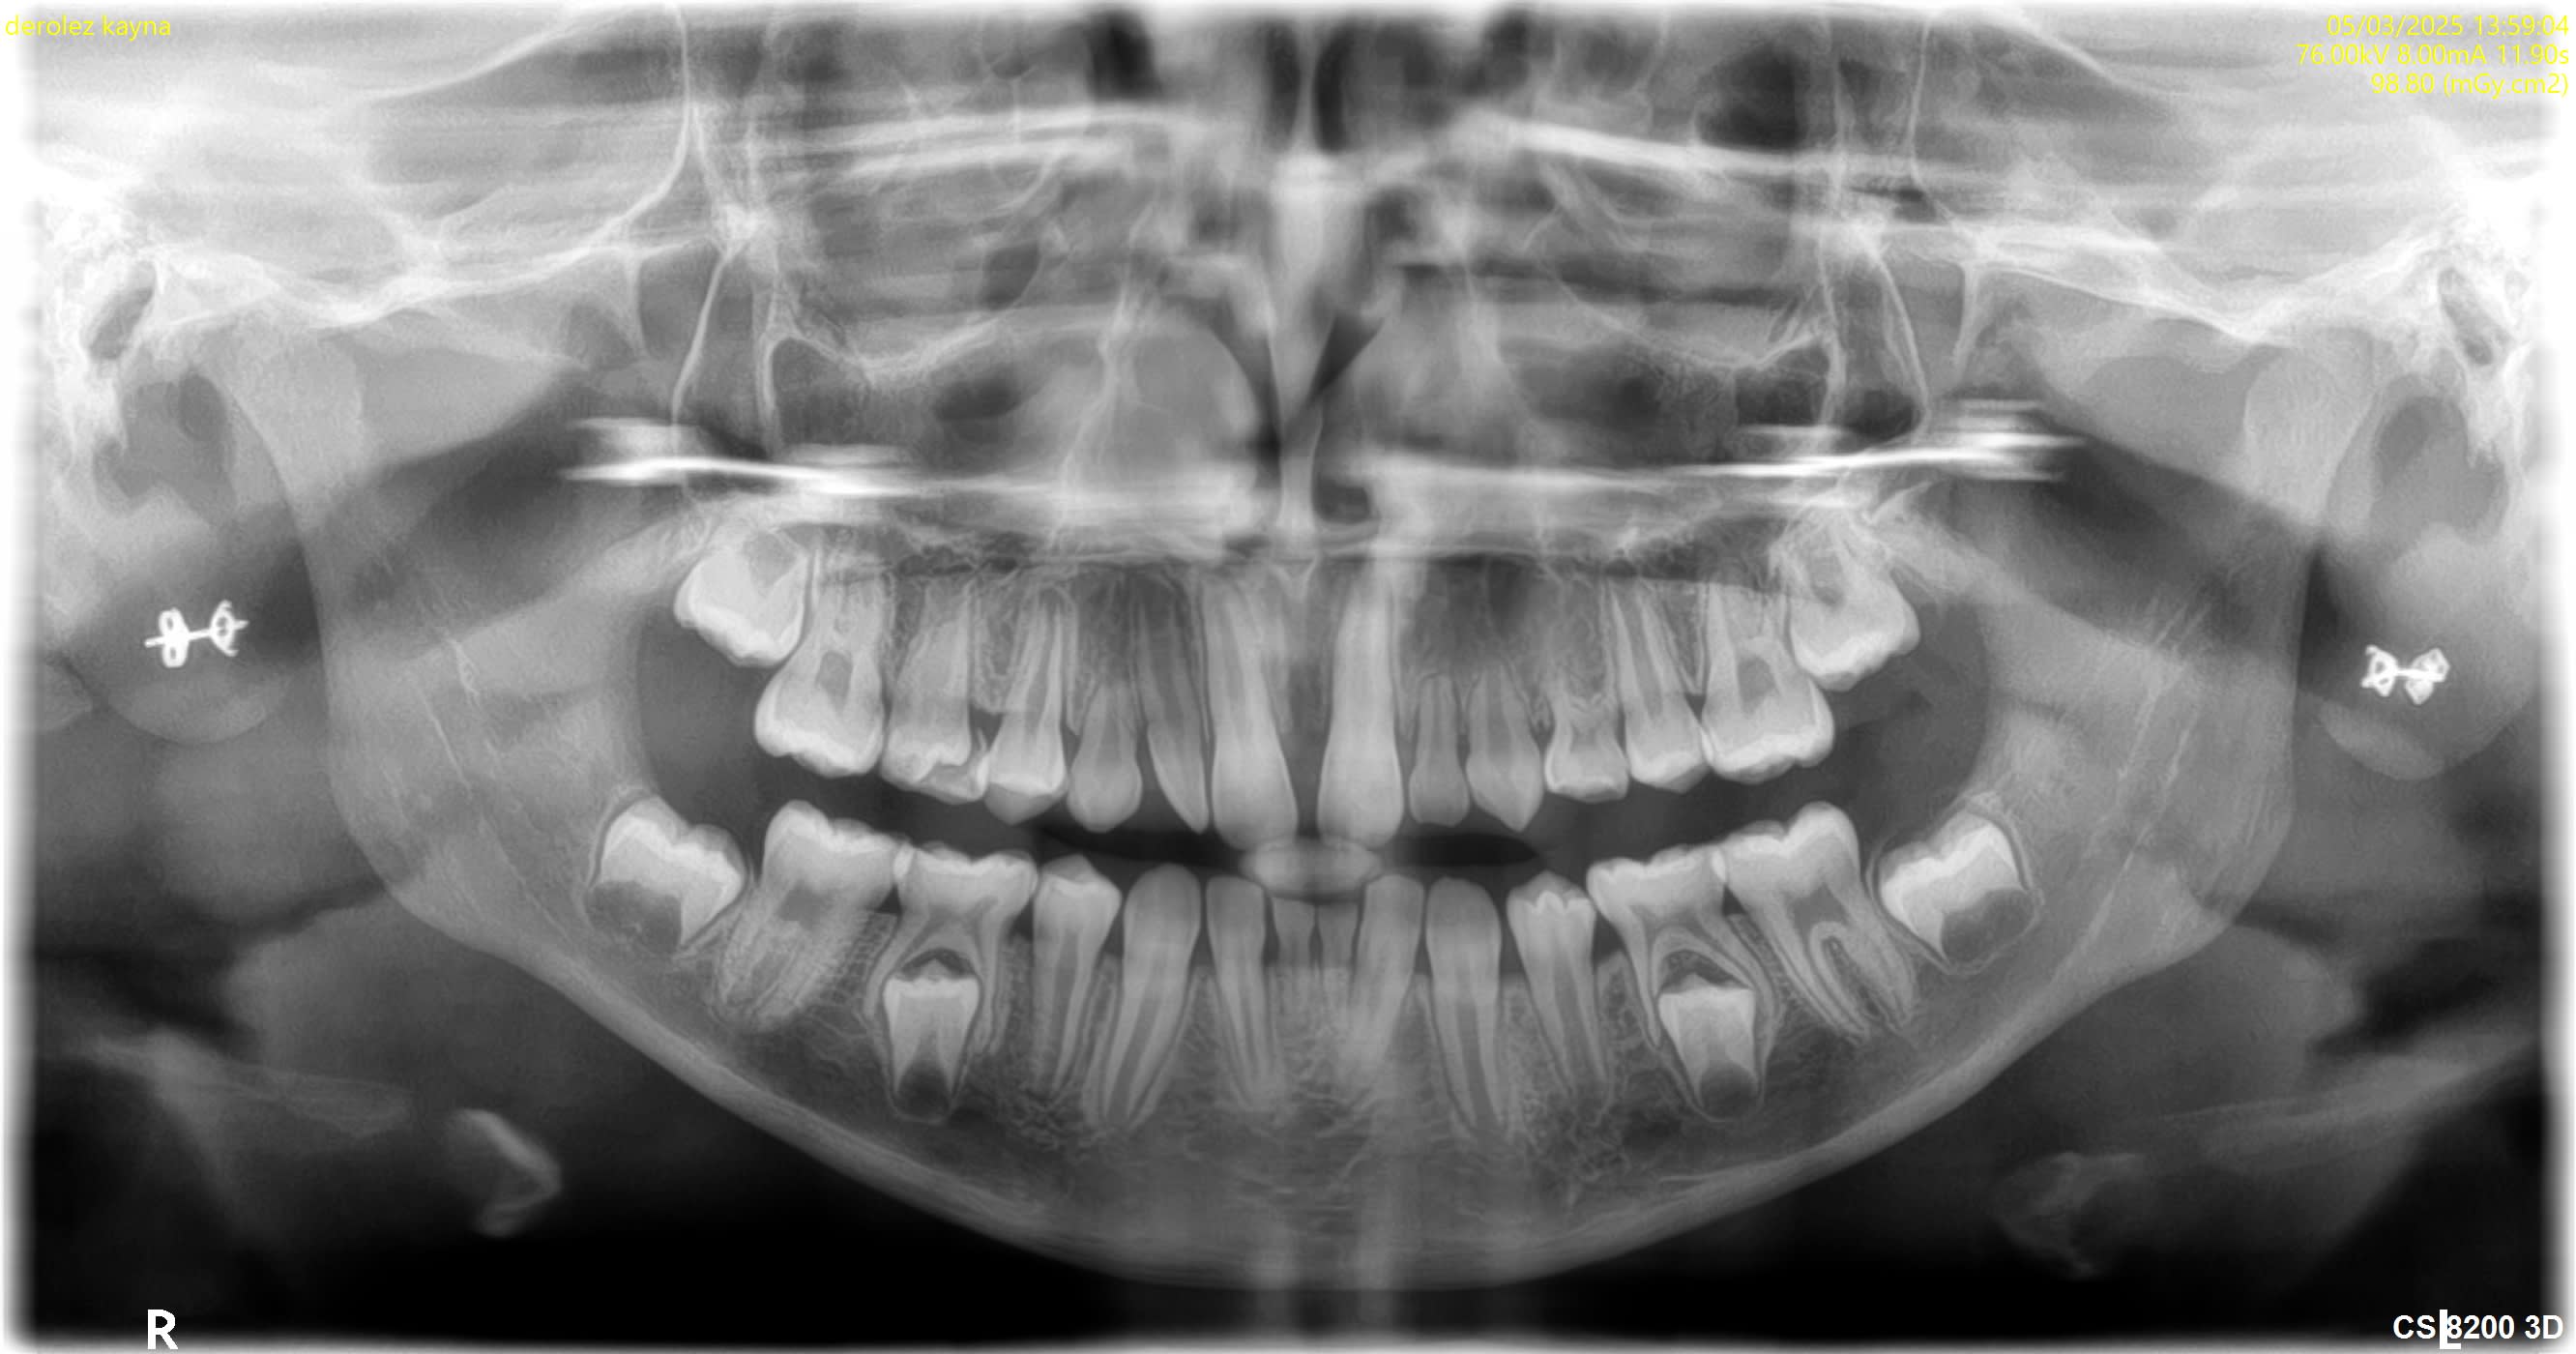

agénésie multiple

Bonjour, comment gérez -vous ce cas dans le temps l' enfant, âgé de 10 ans ?

En cas d'oligodontie, une recherche de syndrome associé est conseillé.

Rapprocher la patiente d'un centre de référence et surtout d'un ODF.